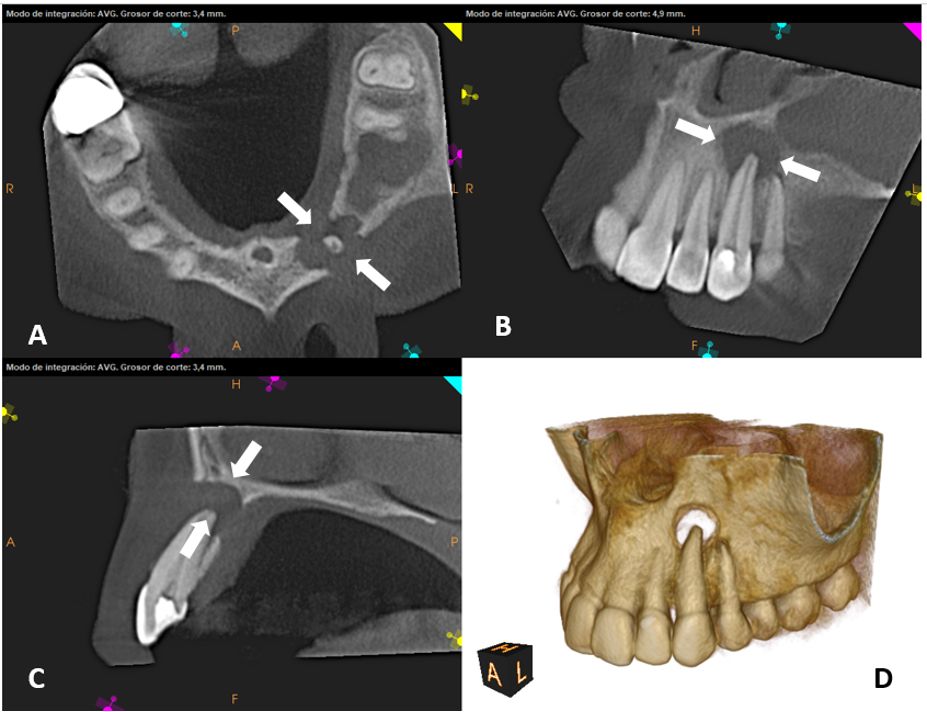

Estudio 3D tercer molar pre-quirúrgico

Evalúa la posición y las complicaciones asociadas con los terceros molares, especialmente en casos de impactación.

Estudio 3D pieza dentaria retenida pre-quirúrgico

Herramienta esencial para diagnosticar y evaluar dientes retenidos, permitiendo una visualización precisa de su posición y relación con estructuras adyacentes.